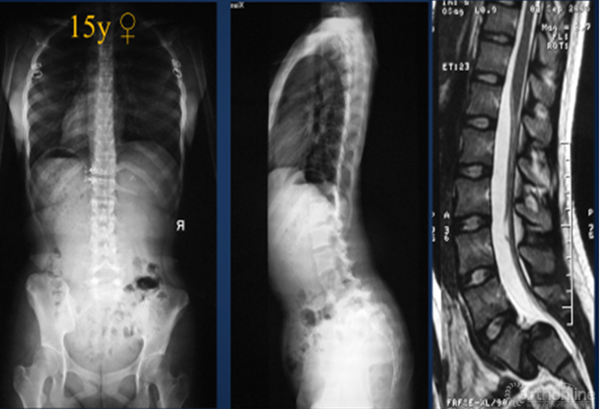

对重度骶骨发育不良者,先天遗传是主要原因。2015年,罗卓荆团队通过两个家系[6],鉴定了2个新型错义突变,功能研究显示软骨发育过程中,磷酸化摄入障碍是其发病主要的分子机制。遗传因素造成的骶骨穹窿形态不良,通常较为严重,并会造成L5椎体梯形变,导致滑脱进展,并使得外科治疗此类畸形较为困难。

2. 骶骨形态不规则

骶骨形态不规则,通常是由于力学因素造成的。2012年,Sevrain[7]根据PI值将滑脱分为低PI组和高PI组,生物力学测试结果表明,低PI组人体重心位于骶骨中后区,而高PI组重心则分布在骶骨前方。从而更容易造成骶骨形态发生轻度或中度形态变化,L5椎体出现相应梯形变,从而亦会造成滑脱进展。